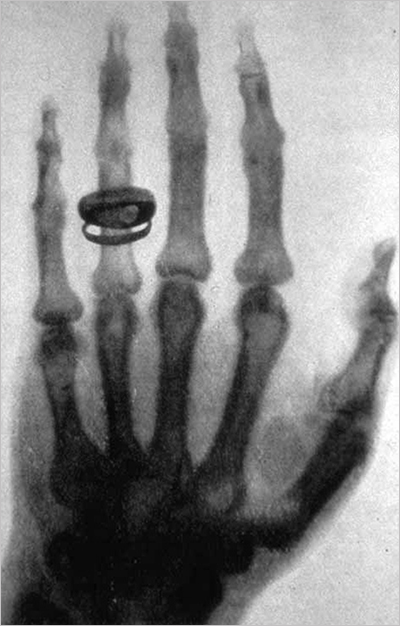

여기서 뢴트겐은 한 가지 아이디어를 떠올리게 되는데, 당시 사진건판이 발명되어 사진관에서 사진을 찍는 것이 유행이었습니다. 뢴트겐은 이 사진건판을 이용하여 새로운 빛을 활용해 감광 사진을 찍는 아이디어를 떠올렸습니다. 그 결과는 우리에게 너무나 잘 알려진 바로 그 사진에 담겨 있지요. 약혼녀의 손을 찍은 이 사진은 뢴트겐에게 새로운 빛이 존재한다는 명백한 증거가 되었고, 이 미지의 빛은 미지의 선이라는 의미로 X선(X-ray)이라고 부르게 되었습니다. 당시 뢴트겐의 X선 발견은 사회적으로 큰 충격이었는데, 사생활을 크게 침해할 수 있다는 걱정과 그에 관련한 광고까지 나왔을 만큼 사회문화적으로 불투명한 물질의 내부를 들여다볼 수 있다는 사실은 적잖은 충격이었습니다.

X선은 발견되자마자 많은 분야에서 활용되었는데요. 최초로 X선을 활용하여 절개 없이 골절을 진단하거나, 머리에 박힌 탄환을 확인하기도 하였습니다. 이전에는 신체 내부의 상태를 확인하기 위해 외과적 수술이 필수였는데, X선의 발견으로 절개하지 않고도 이를 확인할 수 있게 된 것입니다. 의학계에서는 페니실린의 발견에 버금가는 혹은 그 이상의 발견이었다고 할 수 있었지요.